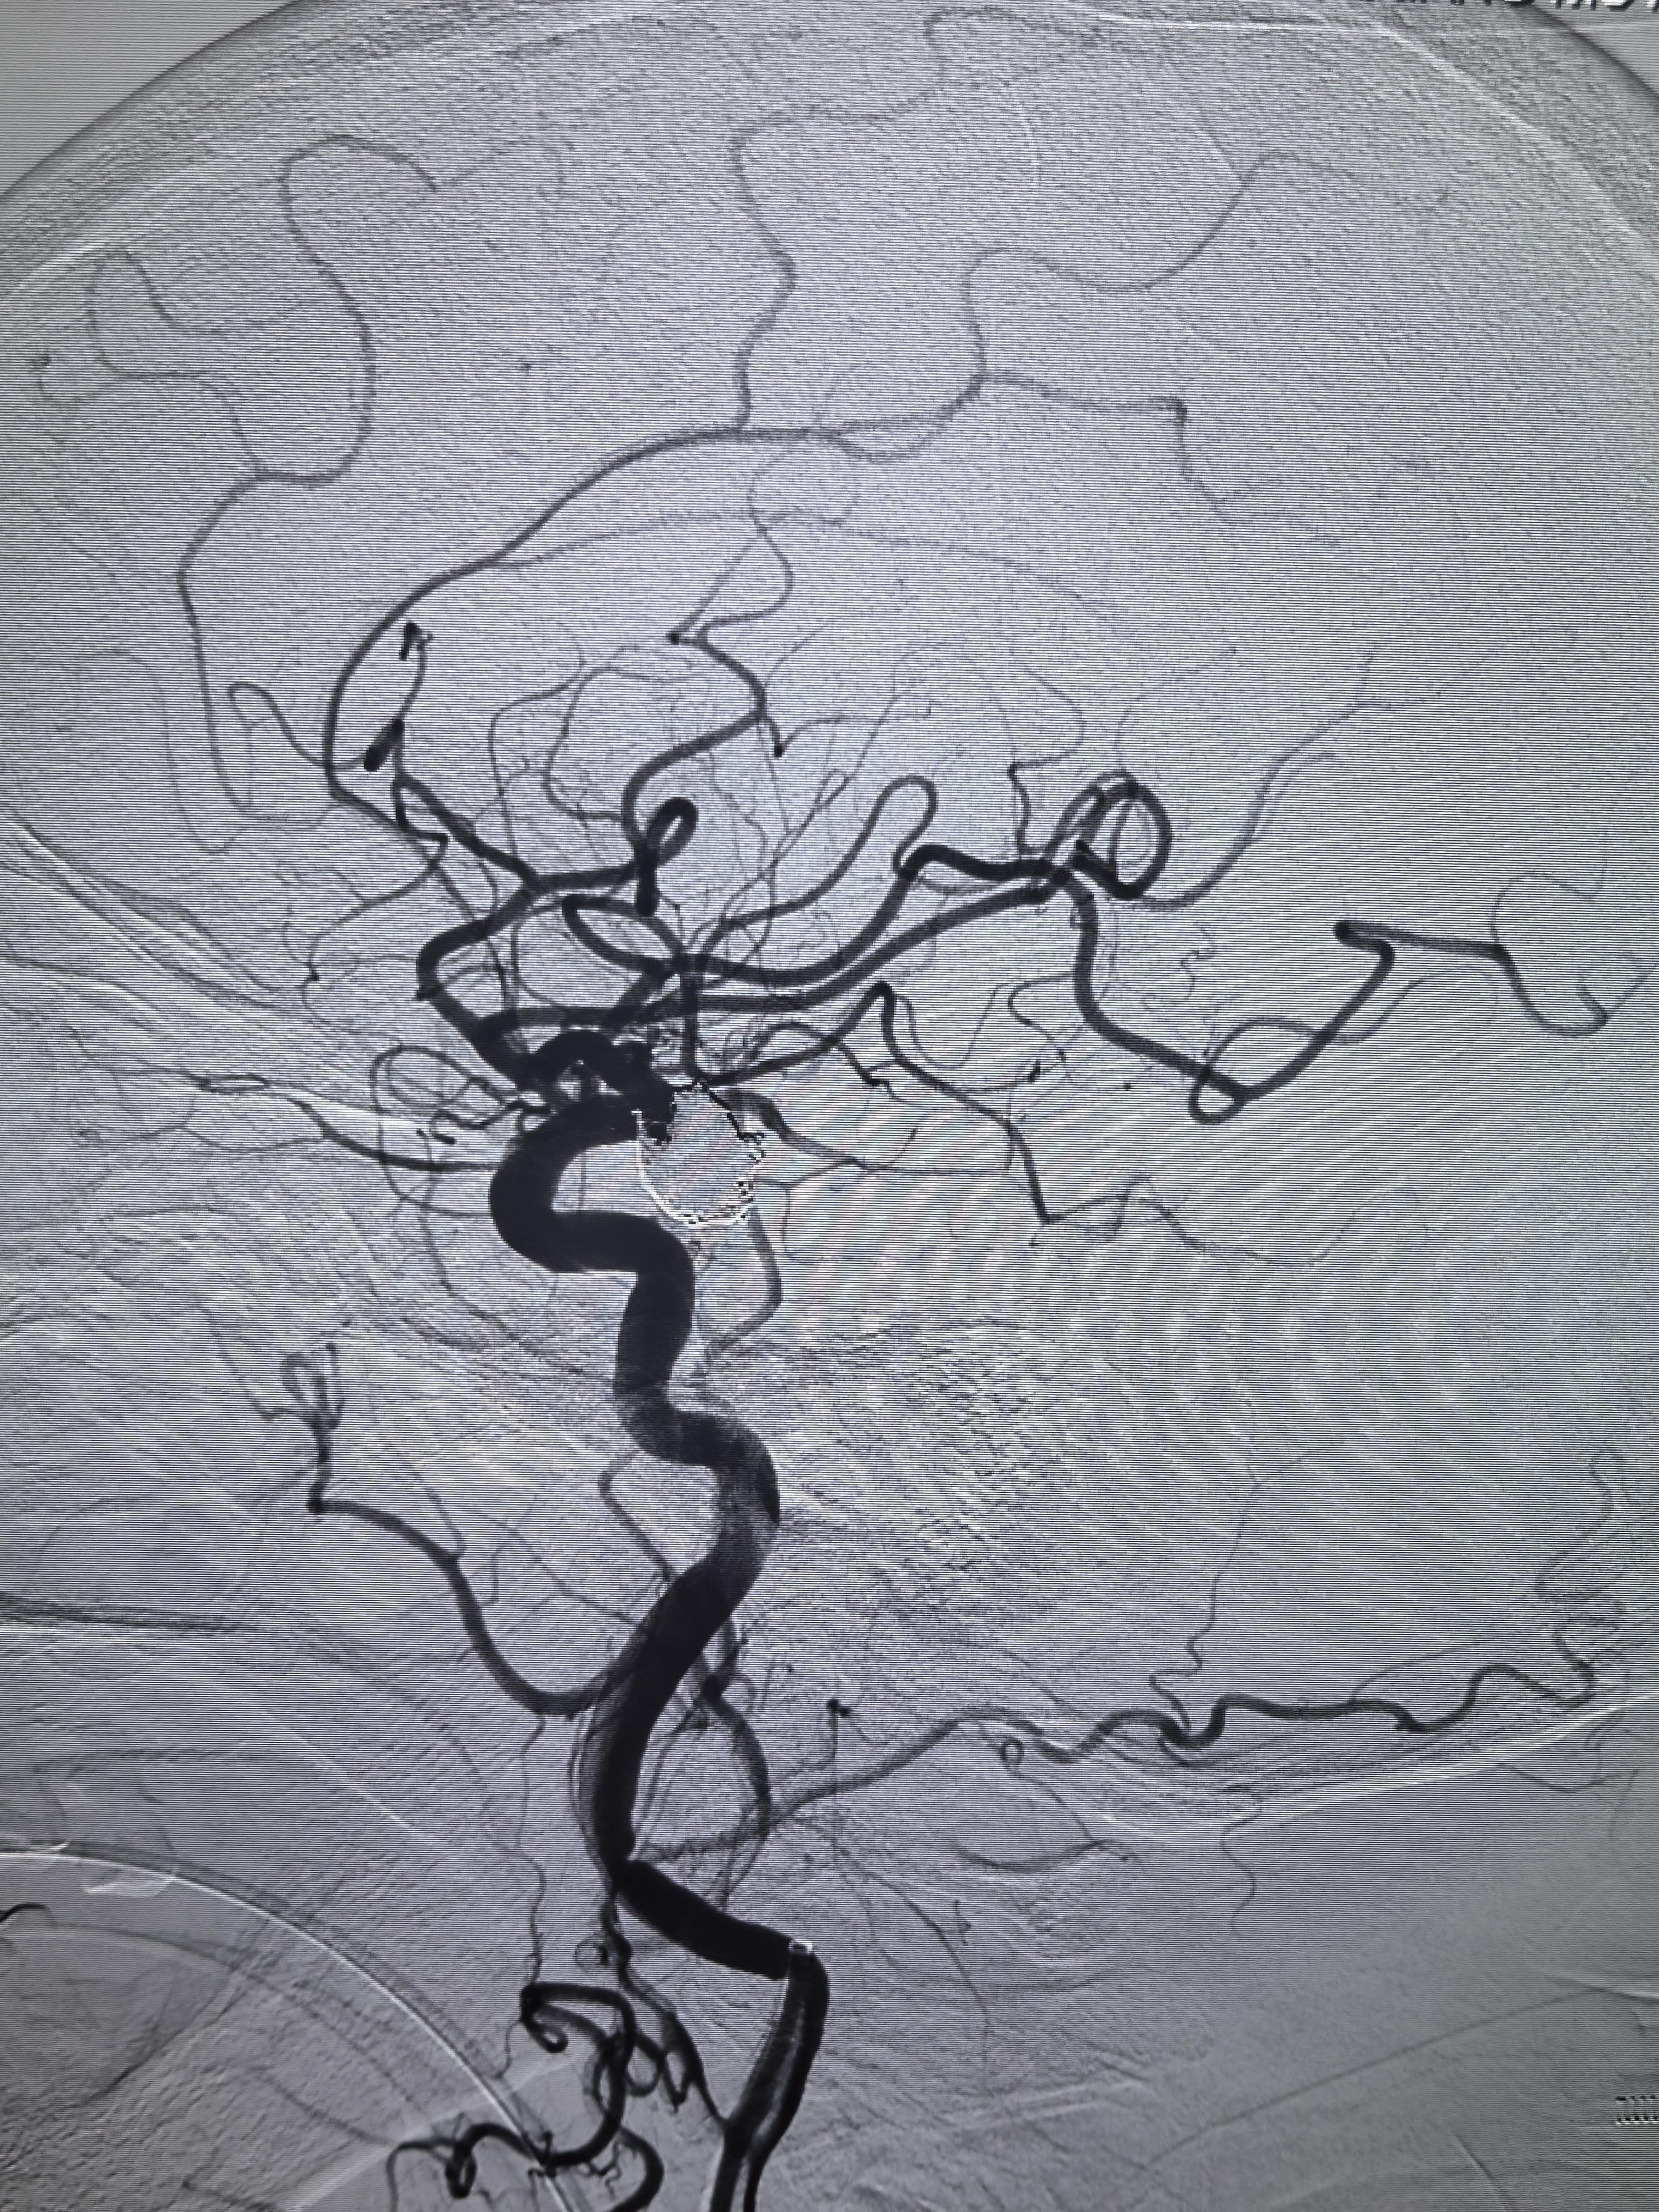

椎基底动脉造影无P1!

压颈试验显示同侧P1,手术难度降低,不用考虑保护胚胎型大脑后动脉瘤了!

术后正位造影!

术后椎动脉造影左侧大脑后动脉显影良好!